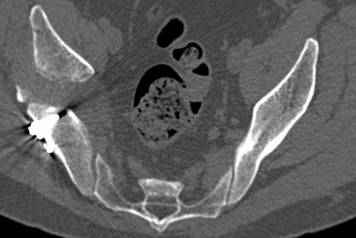

высылаю дополнительно сканы.

По отдельным срезам и тем более по реконструкции трудно судить о сращении крыла и задней колонны с осевым скелетом.

В большинстве случаев при двухколонных переломах

в итоге получается прочный бублик с дыркой. При эндопротезировании в дырку помещается головка, а чашка должна неплохо заклиниться в бублике.

Главное, чтобы бублик не был разорван, что не очень понятно на представленных снимках.

Поэтому хотелось бы дообследовать больного (разумеется включив стандартные проеции judet,и срезы показывающие сращение)

Хорошо бы на рентгенограммы взглянуть и побольше срезов по своду. С каким отломком головка контактирует и как ее состояние.

Из того минимума, что представлено, мне кажется, мы имеем дело с двухколонным переломом вертлужной впадины. Обычно медиальный (центральный) "вывих" головки встречаются в сложных двухколонных переломах со смещением.